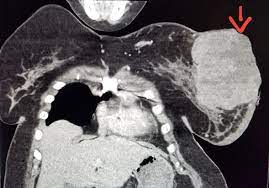

Breast Mass Found On Ct Scan Ct Scan Machine from sites.google.com Understanding pathology for breast cancer. Studies have shown that ct can be effective in both colorectal cancer screening. Each has its own strengths. A ct scan shows organ tear and organ injury more quickly, so it may be more suitable for trauma cases. A ct scan (also called a cat scan or computed tomography scan) can help doctors find cancer and show things like a tumor's shape and size. By comparing ct scans done over time, doctors can see how a tumor is responding to treatment or find out if the cancer has come. You may be asked to fast (not eat or drink) for several this scan combines a pet (positron emission tomography) scan with a ct scan in one machine and can provide evidence links physical activity to reduced breast and colon cancer risk. Ct scan is short for computerized tomography scan.

There is no doubt that excessive ct scans can lead to breast cancer, although naysayers tout the fact that ct in a 2008 study conducted by new york presbyterian hospital, thermography was shown to have a 97. Ct scans can show a tumor's shape, size, and location. Often these findings indicate a need for. Ct scans are usually done at a hospital or radiology clinic. Studies have shown that ct can be effective in both colorectal cancer screening. Most current mri machines cannot rapidly scan the brain to help determine the cause of a stroke (ischemic versus hemorrhagic). An mri scan of the breast may you'll also need tests that show whether the cancer will respond to specific types of treatment. Diagnose and assess breast tumors. Ct scans are inaccurate for treatment monitoring after cancer treatment, a ct scan is unable to determine whether masses leftover are cancerous: The results of these tests can give your doctors a. The scan is painless and takes about 10 to 30 minutes. For example, it could be scar tissue left over from cancer killed off by. A ct scan may be used to look for tumors in organs outside of the breast, such as the lung, liver, bone, and lymph nodes.

The results of these tests can give your doctors a. In some cases, physicians use all three imaging techniques. What can a ct scan show that an mri cannot? A ct scan can show possible concerning findings based on a radiologist's interpretation of what is seen. A ct scan can show whether breast cancer has spread to the lungs or liver. Ct scans can show a tumor's shape, size, and location. A radiographer operates the scanner. Digital breast tomosynthesis (dbt) was introduced in 2011 and approved by the fda for breast cancer screening and diagnosis. Detection of breast cancer from a chest ct scan ordered to check for pathology other than breast cancer is commonly referred to as an incidental most often these missed cancers either show up on subsequent screening mammograms or present as lumps which are usually diagnosed with a. For example, it could be scar tissue left over from cancer killed off by. For patients showing up in the emergency. At the low doses of radiation a ct scan uses, your risk of developing cancer from. A computed tomography (ct or cat) scan allows doctors to see inside your body.

Ct scans can show a tumor's shape, size, and location. A ct scan of the middle abdomen showing a large tumor mass due to metastasis (spreading cancer) in abdominal lymph nodes. A ct scan may be used to look for tumors in organs outside of the breast, such as the lung, liver, bone, and lymph nodes. A computed tomography (ct or cat) scan allows doctors to see inside your body. Diagnose and assess breast tumors.